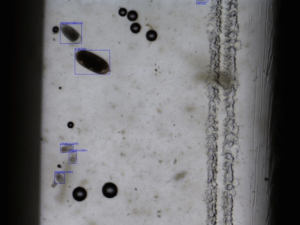

In the next of our 6 part OvaCyte Blog Series, we delve deeper into our Speciation offering, focusing on Nematodirus Battus and how OvaCyte can support your parasite control programmes! The word Battus finds its origins from Libyan kings, Greek cattle thieves, and German gold. Which is appropriate given that Nematodirus battus eggs are king-sized compared to other strongyle eggs and give off a gold hue when observed under the microscope.

Image courtesy of Ovacyte™